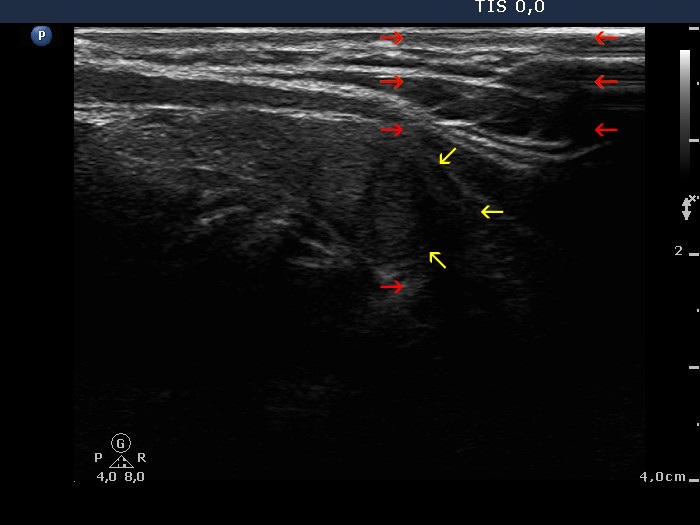

Bening colloid goiter - case 2119

Wrong settings

Right settings

This case illustrates the significance of two issues, an avoidable and an unavoidable cause of non-pathological blur. Regarding the former let's compare the upper images. We can see that both the focus was improper and the general setting was also set incorrectly to 'R' (resolution, i.e., to higher frequency). After proper focusing and proper setting to 'P' (penetration, i.e. to lower frequency), the dorsal blur of the image has disappeared in the right image. On the other hand, the nodule was relatively large and even if the settings are good, we can't make the lower part of the nodule clearly visible.